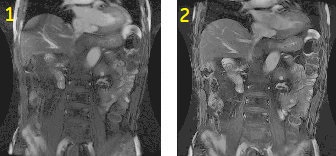

Figure 4. Abdominal image comparison

Table 3. Image legend Number Description 1 No shimming prior to the acquisition. 2 Shimming prior to scanning. Notice the absence of the band-like artifact on the image.